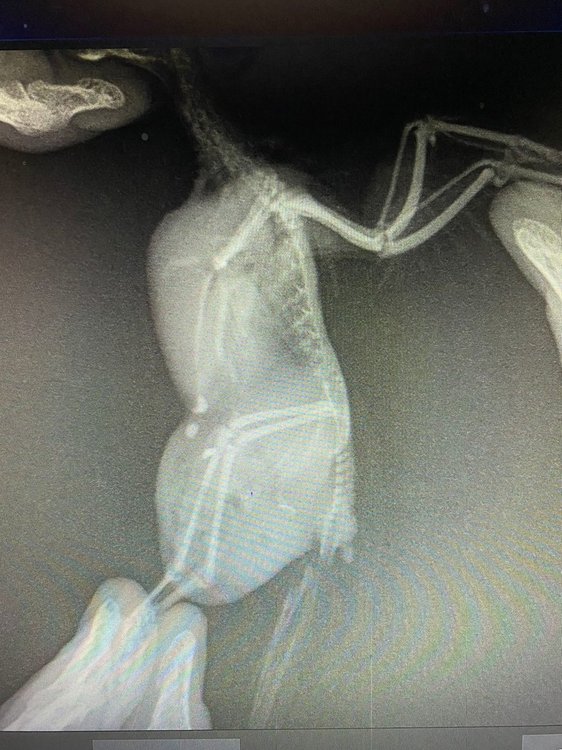

@Delfin Здравствуйте, спасибо за ответ. Вчера уже съездили к ветеринару и сделали рентген, сказали неоперабельная опухоль, не знаю, может врач и ошибается

7DC8KEAXxtc.thumb.jpg.26253b621bf72ff12f30ddb8e46e7533.jpg